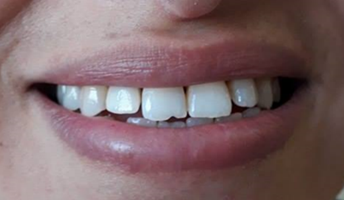

The final cementation was carried out using adhesive resin cement. The patient was satisfied with the esthetic appearance.

Figure 8: Final Result.